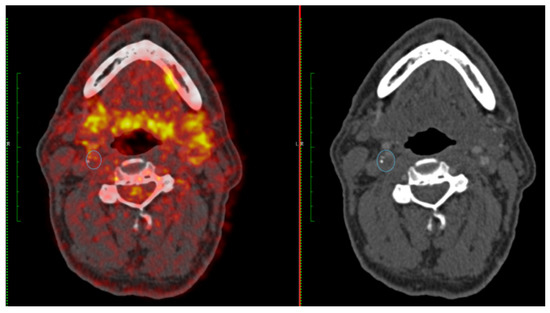

4. Development of FDG-PET Imaging as a Marker of Plaque Vulnerability

- Moustafa, R.R.; Izquierdo-Garcia, D.; Fryer, T.D.; Graves, M.J.; Rudd, J.H.; Gillard, J.H.; Weissberg, P.L.; Baron, J.C.; Warburton, E.A. Carotid plaque inflammation is associated with cerebral microembolism in patients with recent transient ischemic attack or stroke: A pilot study. Circ. Cardiovasc. Imaging 2010, 3, 536–541. [Google Scholar] [CrossRef]

- Marnane, M.; Merwick, A.; Sheehan, O.C.; Hannon, N.; Foran, P.; Grant, T.; Dolan, E.; Moroney, J.; Murphy, S.; O’Rourke, K.; et al. Carotid plaque inflammation on 18F-fluorodeoxyglucose positron emission tomography predicts early stroke recurrence. Ann. Neurol. 2012, 71, 709–718. [Google Scholar] [CrossRef] [PubMed]

- Kelly, P.J.; Camps-Renom, P.; Giannotti, N.; Marti-Fabregas, J.; Murphy, S.; McNulty, J.; Barry, M.; Barry, P.; Calvet, D.; Coutts, S.B.; et al. Carotid Plaque Inflammation Imaged by (18)F-Fluorodeoxyglucose Positron Emission Tomography and Risk of Early Recurrent Stroke. Stroke 2019, 50, 1766–1773. [Google Scholar] [CrossRef]